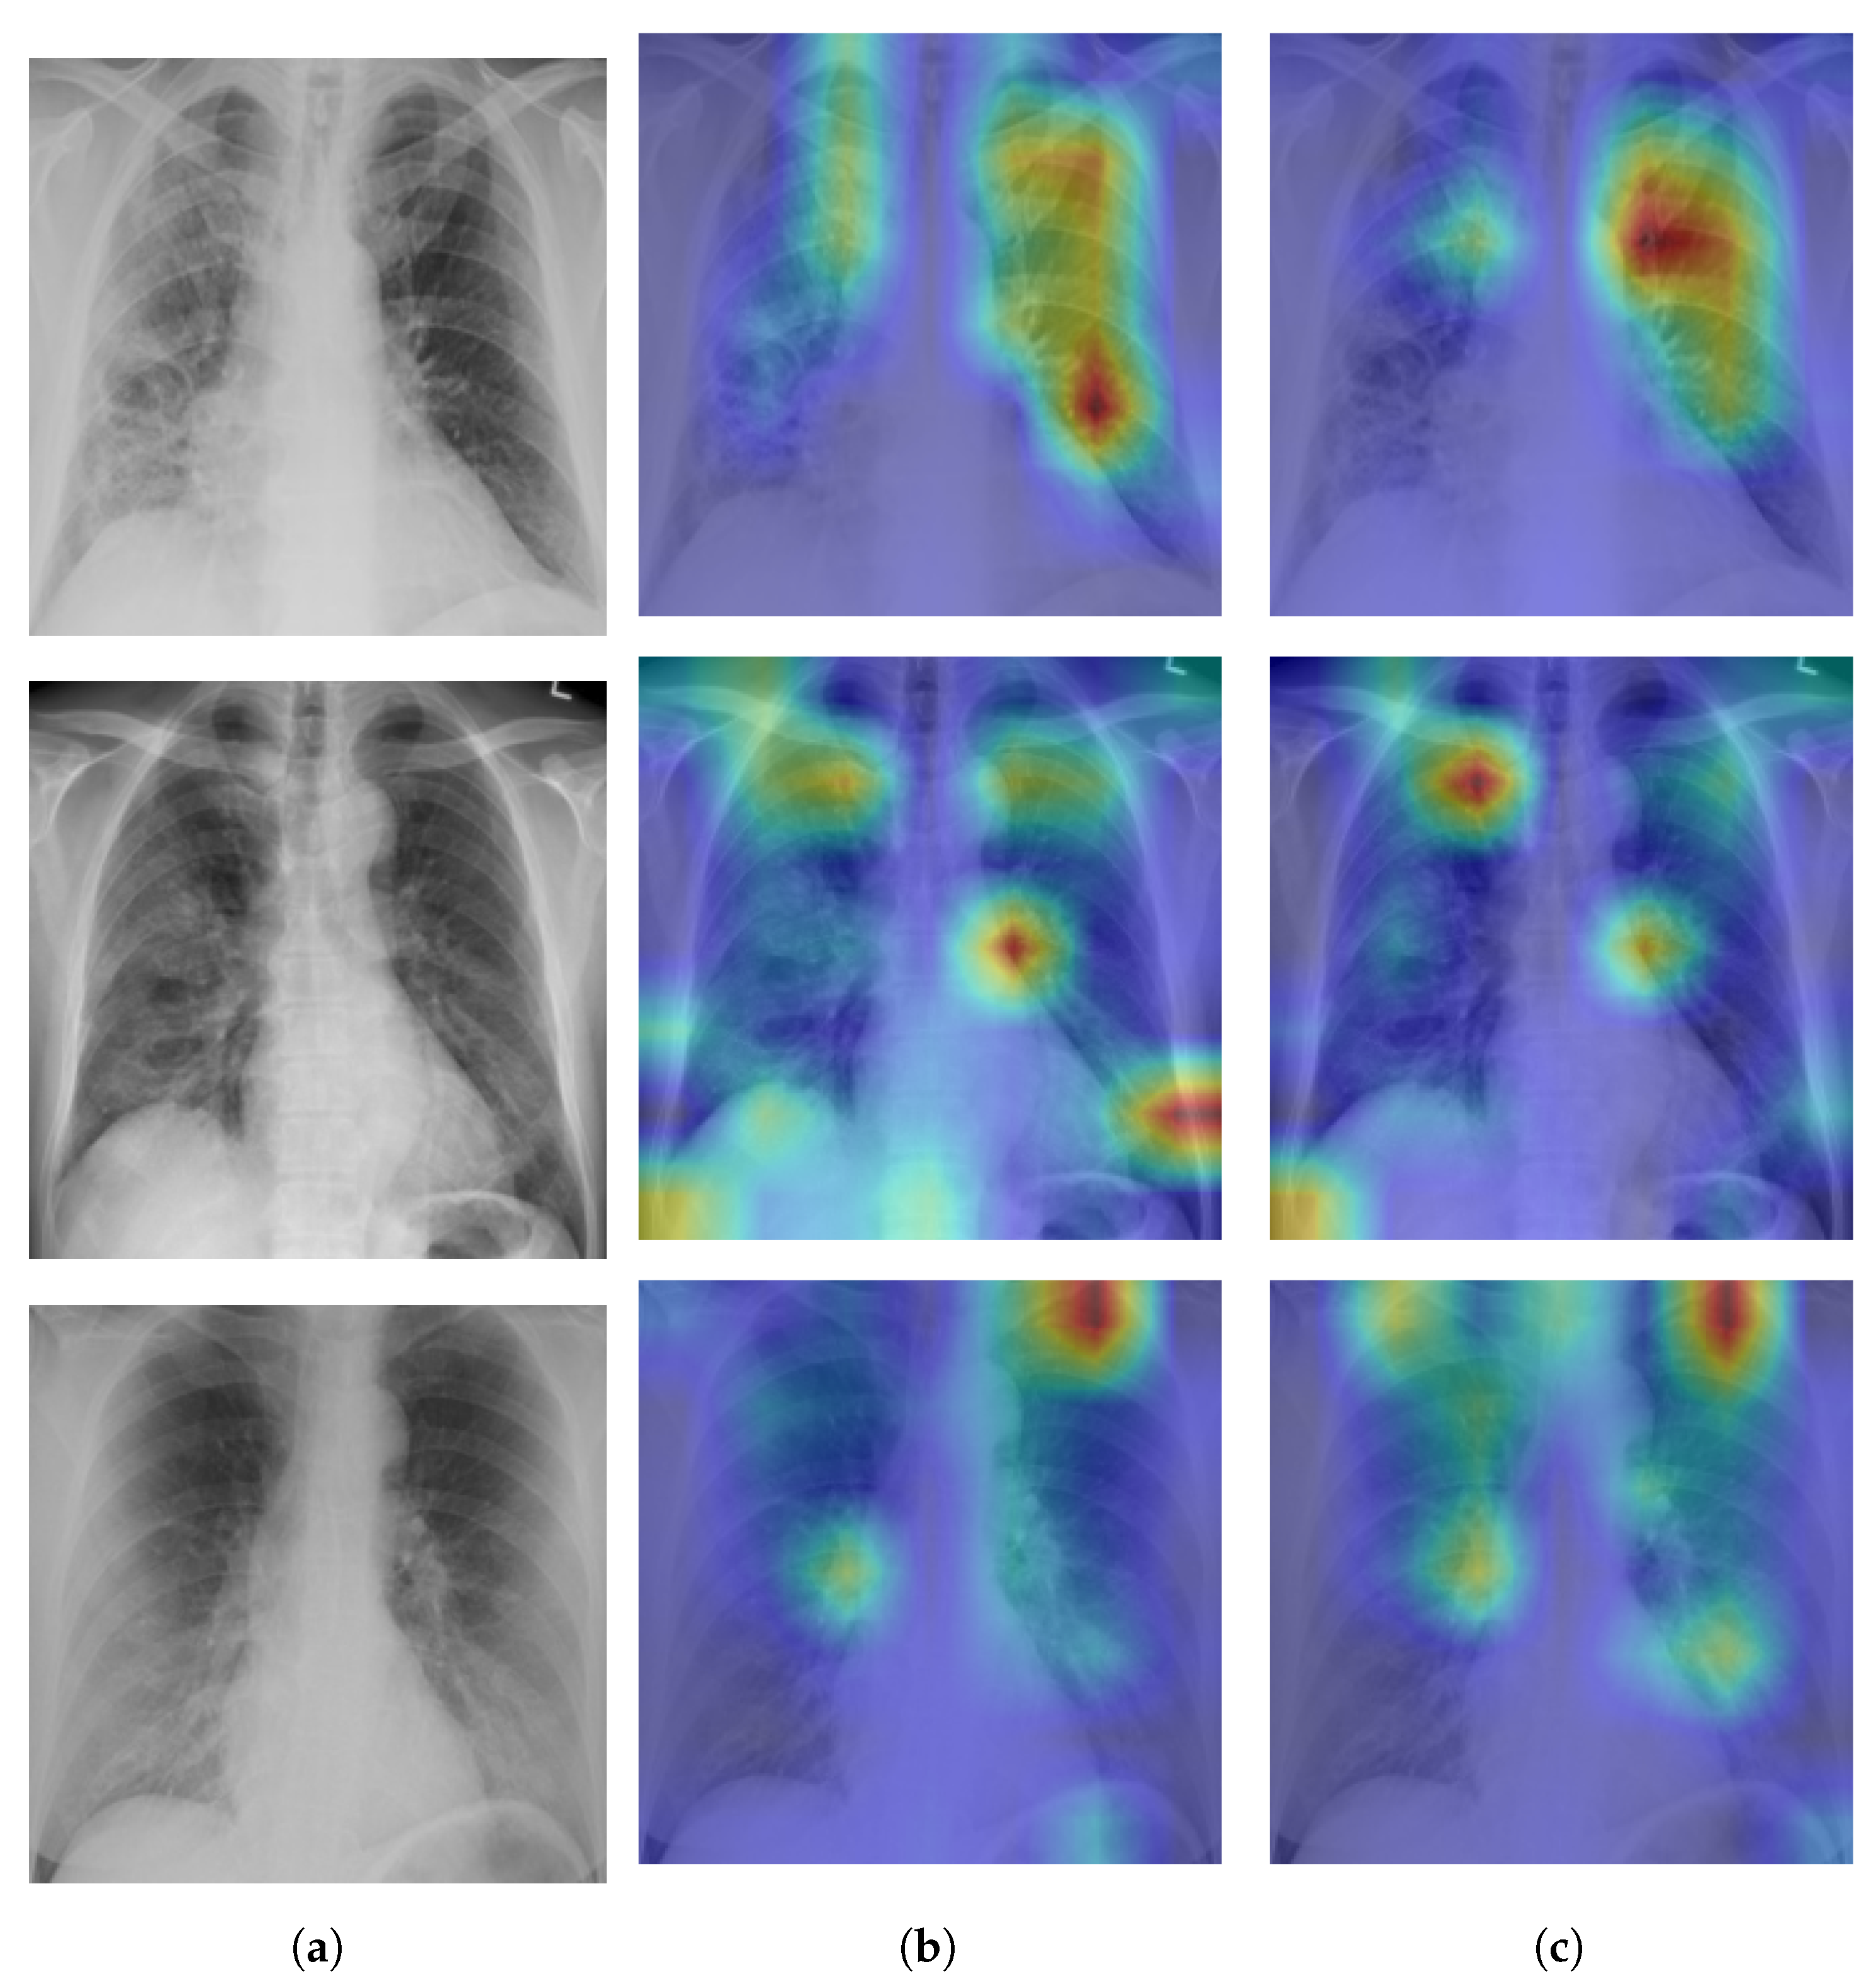

8. Model Explainability

A Self-Attention with MLP module and a Standard Transformer Encoder make up the visual transformer. We visualised the signs recognized by ViT using the attention map of ViT-B32 in order to better understand how the model learned to recognize the COVID-19 signs. The self-attention score for the model can be used to visualize the input image. In this investigation, the jet colour scheme is employed. The blue tones in this colour scheme indicate lower values, which indicate that no features are extracted for a particular class, while the yellow and green tones indicate medium values, which demonstrate an intermediate probability for being in a particular class; the red and dark red tones indicate higher values, which indicate that the features in the region correspond to the particular class. Figure 9a shows samples of true positives with the attention map. The images demonstrate that the affected area was highlighted more precisely by the P2PFL than by non-P2PFL model. This shows that after the model aggregation of the two hospitals, we obtain a robust model to detect signs of COVID-19. The detection of signs becomes more accurate if high resolution CXR images are used.

Figure 9. Example of explainability COVID-19 cases on hospital-1 and hospital-2 using P2PFL and non-P2PFL: column (a) original images, (b) TP COVID-19 cases for non-P2PFL, (c) TP COVID-19 for P2PFL.